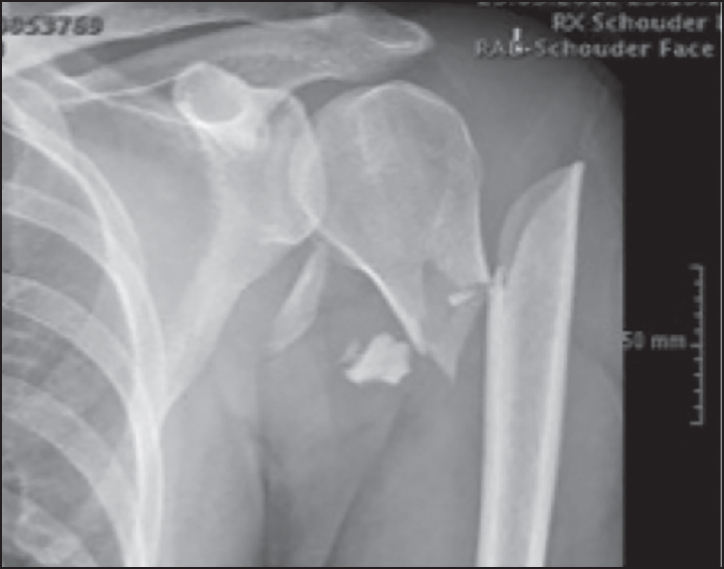

A 33-year-old man was injured in his upper body by a falling metal fence. He was admitted to the emergency department of the University Hospital Ghent. Clinically, he had no apparent neurovascular dysfunction of the left arm. More specifically, the sensory function of the axillary nerve was normal. Motor evaluation of the upper arm was impossible due to pain inhibition. Plain X-ray [Figure 1] showed a comminuted two-part surgical neck fracture of the humerus, with a proximal, lateral and posterior displacement of the humeral shaft. Computed tomography scan confirmed this position of the distal part and showed an undisplaced fracture of the greater tuberosity. | Figure 1: Plain anteroposterior X-ray of the two-part surgical neck fracture. Notice the proximal and lateral displacement of the distal fragment, further than the lateral cortex of the proximal fragment

Click here to view |